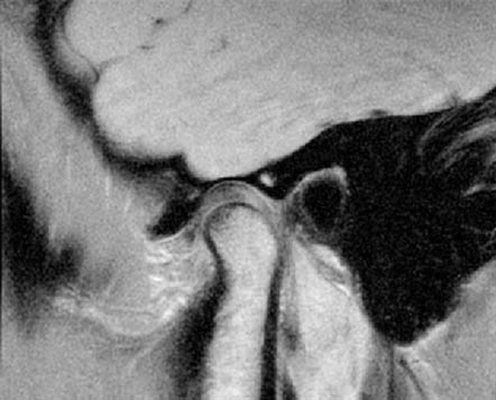

На МРТ представлен нормальный ВНЧС

Магнитно-резонансная томография - современный метод визуализации структур организма. На вопрос: «МРТ челюсти, что показывает?» - можно ответить, что она отражает не только состояние височно-нижнечелюстного сочленения, но и окружающих мягких тканей лица. Метод основан на взаимодействии магнитного поля и диполей воды. Интенсивность сигнала, поступающего обратно к датчикам, зависит от насыщенности тканей жидкостью. Компьютерная программа обрабатывает информацию, и специалисты получают снимок высокого разрешения с возможностью построения трехмерной модели.

Во время МРТ височно-нижнечелюстного сустава (ВНЧС) обследуемая область сканируется послойно. Толщина среза от 1 мм. Высокая разрешающая способность в полной мере отразит строение мягкотканных структур: капсулы, связок, внутрисуставного диска, жевательных мышц. Доктор оценивает функциональное состояния ВНЧС и отклонения от нормы: